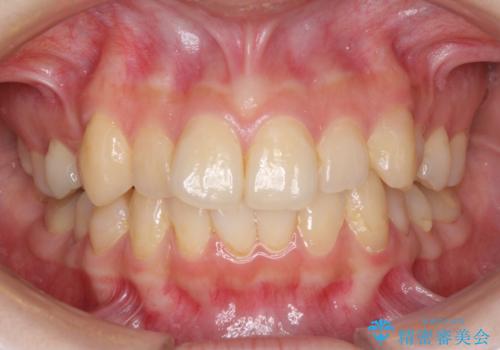

前歯のがたつきをインビザラインで目立たない矯正